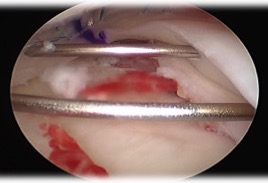

- insert graft bone into slot

- secure with screw

- flip meniscus